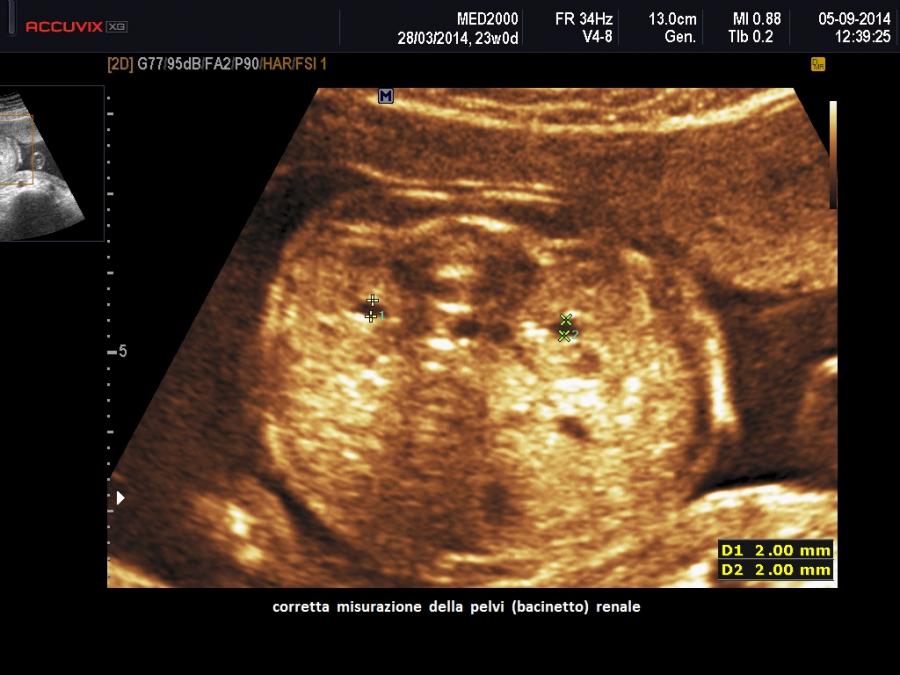

• pielectasia e calicectasia: consiste nella dilatazione della pelvi o bacinetto e dei calici; la diagnosi di pielectasia è effettuata allorquando il diametro antero-posteriore della pelvi è superiore ai 7 mm. Nelle forme severe di pielo-calicectasia si ha compressione del parenchima renale con successiva corticalizzazione.